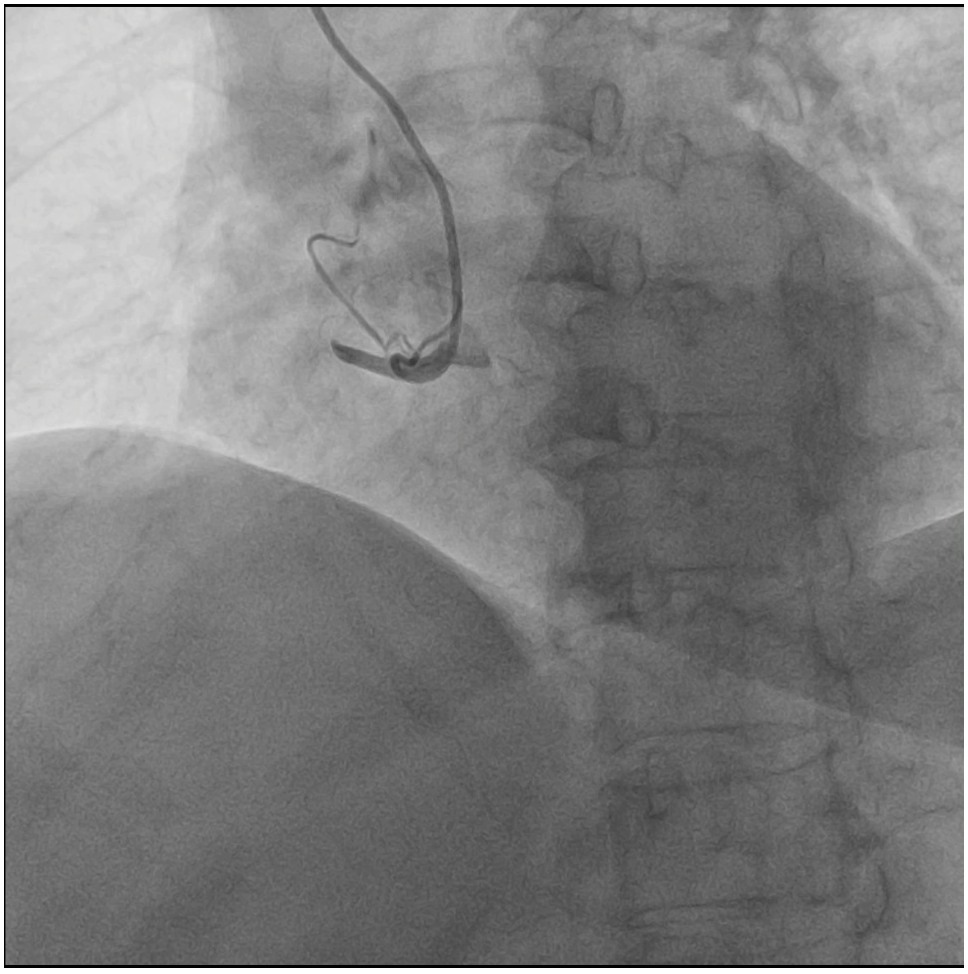

Relevant Catheterization Findings

The diagnostic angiography demonstrated a severely tortuous coronary vessels, moderate lesion at LAD and LCX, total occlusion at proximal RCA with no traces of collaterals from the ipsilateral or contralateral circulations.